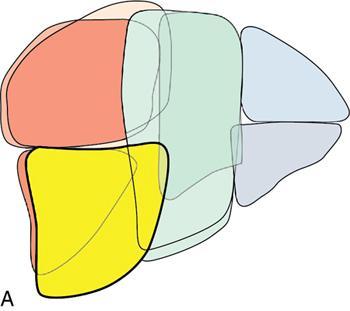

Ritu K. Kashikar, Shrinivas B. Desai Imaging is the mainstay of noninvasive diagnosis of the spectrum of abdominal pathologies or proving absence off thereof. Knowledge of normal anatomy and important normal variants is thus essential for the radiologist in order to avoid misinterpretation or erroneous diagnosis. This chapter highlights the normal anatomy of the hepatobiliary systems including the blood vessel and draining ducts and discusses relevant anatomical variants which may have important clinic implications. The liver is the largest abdominal organ, occupying the right upper abdominal quadrant and is in close approximation with the diaphragm, stomach and the gallbladder. It is largely covered by the costal cartilages. The liver is encapsulated by Glisson’s capsule which is a dense layer of connective tissue. It is covered by peritoneum, except in the regions of gallbladder fossa, fossa for inferior vena cava (IVC), and the bare area. The bare area is the posterocranial aspect of the liver, adjacent to the dorsal body wall, which is not covered by peritoneum. The liver has two surfaces, the convex diaphragmatic surface and a concave visceral surface. The slit in the hepatic hilum is called the porta hepatis and is penetrated by the right and left hepatic ducts (LHDs), hepatic artery and portal vein (PV). The distal portion of the lesser omentum is called the hepatoduodenal ligament and contains the common bile duct (CBD), hepatic artery, PV, nerves of liver and lymphatics. The liver has dual blood supply with hepatic artery providing 25% of hepatic blood and rest by portal vein (Fig. 9.2.1). Five ligaments connect the liver to the undersurface of the diaphragm. These include the falciform, the coronary and two lateral ligaments, all of which are peritoneal folds. The fifth ligament is a fibrous cord-like structure and represents the obliterated umbilical vein. The peritoneum invaginates into the liver parenchyma leading to formation of fissures. There are four normal fissures: fissures for the ligamentum teres, ligamentum venosum and gallbladder and the transverse fissure (Fig. 9.2.2). The liver is organized into microscopic functional units called lobules or acini. A central terminal hepatic venule surrounded by four to six terminal portal triads form a polygonal unit called the hepatic lobule. The terminal portal triad branches line the periphery of the unit. Between the terminal portal triads and the central hepatic venule the hepatocytes are arranged in one cell thick plates, surrounded by sinusoids. The blood flows from the terminal portal triad through sinusoids into terminal hepatic venule. Bile formed within the hepatocytes empties into terminal canaliculi which coalesce into the bile ducts (Fig. 9.2.3). This structure of the functional hepatic unit forms the basis of various functions of the liver. The normal relations of the liver are: The liver can be divided into right, left and caudate lobes. The right and left lobes are separated by the interlobular fissure and is oriented along a line passing through the gallbladder fossa inferiorly and the middle hepatic vein (MHV) superiorly (Fig. 9.2.4). This plane runs from the left of the IVC to the left of the gallbladder fossa and is a called the Cantlie’s line. Use of standardized, segmental anatomy is imperative because it facilitates communication and treatment planning. The segmental anatomy of liver is primarily based on vascular anatomy. The right lobe is divided into anterior and posterior sectors by of the right hepatic vein (RHV). The left lobe is divided into medial and lateraI sectors by an oblique plane connecting the left hepatic vein (LHV) and the falciform ligament. The liver is divided into upper and lower segments at the level of main portal vein (MPV) bifurcation (Fig. 9.2.5). Various systems are used in classification of liver anatomy. These are discussed in Table 9.2.1. The Couinaud’s system is the most commonly used and divides eight sections/segments which are discussed in details below (Table 9.2.2). 1. Segment 1 – Caudate lobe Bounded anteriorly and medially by the fissure for ligamentum venosum (Fig. 9.2.6). 2. Segment 2: Superior segment of the left lateral sector/section Bounded medially by falciform ligament and inferiorly by plane of MPV, also known as the posterior lateral sector (Bismuth, FCAT) (Fig. 9.2.7). 3. Segment 3: Inferior segment of left lateral sector/section Bounded medially by the falciform ligament and superiorly by the plane of the MPV bifurcation, also referred to as lateral anterior sector (Bismuth, FCAT) (Fig. 9.2.8). 4. Segment 4: Left medial sector/section Bounded laterally by falciform ligament and medially by Cantlie’s line (Fig. 9.2.9). 5. Segment 5: Inferior segment of the right anterior sector/section Bounded anteriorly by the gallbladder fossa and posteriorly by the plane of the RHV, superiorly bounded by the plane of MPV bifurcation (Fig. 9.2.10). 6. Segment 6: Inferior segment of the right posterior sector/section Bounded anteriorly by plane of the RHP and superiorly by the plane of the MPV bifurcation (Fig. 9.2.11). 7. Segment 7: Superior segment of the right posterior sector/section Bounded anteriorly by the plane of the RHV and inferiorly by the plane of the MPV bifurcation (Fig. 9.2.12). 8. Segment 8: Superior segment of the right anterior sector/section Bounded anteriorly by the plane of the gallbladder fossa and MHV, posteriorly bounded by the plane of the RHV and inferiorly by the plane of the MPV bifurcation (Fig. 9.2.13). Owing to its broad area of contact with the anterior abdominal wall, the liver is an ideal organ for evaluation with sonography. Ultrasound is commonly used for evaluation of size of the liver. On longitudinal scans obtained through the midhepatic line, if the liver measures 13 cm or less, it is normal in 93% of individuals (Fig. 9.2.14). The size of liver in various planes is discussed in chapter on normograms. When the area of contact between the liver and the anterior border of the right kidney, exceeds below two thirds of the kidney, the liver is considered as enlarged. The normal liver is homogeneous with fine echoes and appears evenly bright. The hepatic veins, PV and fissures interrupt the homogeneity of the liver parenchyma (Fig. 9.2.15). The parenchymal echogenicity may vary depending on the equipment, transducer and gain settings and should be judged by comparison with internal references like right renal cortex, body of the pancreas and PV walls. When compared with the adjacent normal right renal cortex the liver normally appears hyperechoic or isoechoic. The pancreas in a young individual is hypoechoic compared to the liver, and isoechoic in middle aged adults. As age progresses and fatty infiltration of the pancreas occurs, the pancreas appears hyperechoic to the liver. The liver is hypoechoic to the spleen. The normal liver reveals a density of 55–65 HU on nonenhanced scan and should appear homogenous with the exception of hypodensity in the regions of vessels and fissures. The liver parenchymal enhancement is minimal the arterial phase, with increase in density by only approximately 10 HU. This phase is usually to access vascular anatomy and to detect neovascular enhancing lesion like HCC, metastasis. Considering the fact that 75% of heptic venous supply is from the PV, the normal hepatic parenchyma shows maximum enhancement in the portal venous phase. During the venous/delayed phase the hepatic attenuation starts falling (Fig. 9.2.16). The hepatic fissures appear as linear fat containing structures. All the four fissures are well identifies on CT (Figs. 9.2.17–9.2.20). Normal liver should demonstrate uniform T1 signal similar or isointense to the paraspinal muscles and slightly hyper intense to the spleen. No signal drop should be seen on in or opposite phase. On T2W1 images liver appears slightly hyperintense to paraspinal muscles, isointense to pancreas and hypointense to spleen (Fig. 9.2.21). Following administration of extracellular contrast agents the normal liver parenchyma enhances on PV phase similar to that seen on CT. The arterial phase is preserved to determining vascular anatomy, variants and tumoural enhancement. Gadoxetic acid (Eovist) and gadobenate dimeglumine (MultiHance) are hepatobiliary agents showing excretion by the liver. In the case of gadoxetic acid, hepatic excretion is ~50%, which allows imaging in the hepatobiliary phase at ~20 minutes following injection. Gadobenate has only 3%–5% biliary excretion with hepatobiliary phase at approximately 40 minutes (Fig. 9.2.22). This property makes these agents useful in detection of nonhepatocyte containing lesions which appear hypointense to background liver on hepatobiliary phase. Hepatic anatomic variants are relatively common and represent normal interindividual variation of liver morphology. Normal Anatomic Variants Anatomic anomalies Accessory and pseudofissures may be seen in the liver. True accessory fissures result from infolding of the peritoneum usually along the undersurface of the liver and are rare. The inferior accessory fissure is the commonest accessory fissure and divides the posterior segment of the right hepatic lobe into lateral and medial portions. Diaphragmatic slips may cause indentation over the liver surface and are not commonly seen on imaging (Fig. 9.2.23). Leftward extension of the lateral segment of the left hepatic lobe appearing as a crescentic density that wraps around the spleen is referred to as sliver of liver. The left lobe of the liver may exhibit various forms: leaf like; spatular; truncated pyramid/wedge shaped; and a bifid appearance (Fig. 9.2.24). Elongated left lobe may be mimic splenomegaly, perisplenic hypoechoic collections or less commonly tumours. Imaging clues to diagnosis are establishing contiguity with liver and visualization of parenchymal vessels coursing through. The portion of the liver that extends medially from the right lobe between the IVC and fissure for ligamentum venosum is called the caudate lobe. The caudate lobe is divided inferiorly into a lateral caudate process and a medial papillary process. The medial papillary process projects medially towards the pancreatic head and has applied importance (Fig. 9.2.25). Riedel’s lobe is a tongue-like projection from the anterior aspect of the right lobe and the most common accessory lobe of the liver. It is seen most frequently in asthenic women. The reported prevalence of RL, ranges from 3.3% to 14.5% and the prevalence is higher in women than in men. It can be 20 cm or more in length and may extend up to the iliac fossa. It is usually asymptomatic and is discovered incidentally (Fig. 9.2.26). Accessory liver lobes are defined as a supernumerary lobe of normal hepatic parenchyma in continuity with the liver. This is a rare entity and usually occurs as a result of congenital ectopic hepatic tissue, although rarely may occur as a result of trauma or surgery. Various systems are proposed for classification of ALL. Another method of classification has been proposed based on biliary drainage and presence or absence of capsule. Accessory lobes can be readily diagnosed and characterized on CT or magnetic resonance imaging (MRI) done for related or unrelated conditions. CT shows the lesion as a soft–tissue density mass attached to the liver and isodense to the organ. The portal/hepatic venous branches can be seen coursing through it, in contiguity with the liver (Fig. 9.2.27). The coeliac axis trifurcates into common hepatic, splenic and left gastric arteries at the level of T12–L1. The common hepatic artery becomes the proper hepatic artery after origin of the gastro-duodenal artery. The hepatic artery proper ascends anterior to the PV and medial to the CBD and divides in to right and left hepatic artery (LHA). Occasionally the middle hepatic (segment 4) artery arises from hepatic artery proper. The hepatic artery appears as a tubular hypoechoic structure and shows antegrade flow on Doppler (Fig. 9.2.28). Normally the resistive index is low ranging between 0.55 and 0.7. The hepatic artery, its anatomy, branches, course, calibre are best evaluated on arterial phase of dynamic CT (Fig. 9.2.29). This is also the preferred modality prior to hepatobiliary surgical planning. Contrast-enhanced MRI also shows the above details but spatial resolution is lower. Road map of the arterial vascularity of the donor and recipient is a prerequisite for transplant surgery and complex hepatobiliary surgery. Detailed hepatic arterial anatomy and its variations have its significance in liver surgeries and interventional hepatic procedures, relative to the hepatic lobe involved. A classification method was described by Michel et al. in 1955, and is discussed in Table 9.2.3 (Fig. 9.2.30). I: standard anatomy ~60% (range 55%–61%) II: replaced LHA ∼7.5% (range 3%–10%) III: replaced RHA ~10% (range 8%–11 %) IV: replaced RHA and LHA ~1% V: accessory LHA from LGA ~10% (range 8%–11%) VI: accessory RHA from SMA ~5% (range 1.5%–7%) VII: accessory RHA and LHA ~1% VIII: accessory RHA and LHA and replaced LHA or RHA ~2.5% IX: CHA replaced to SMA ~3% (range 2%–4.5%) X: CHA replaced to LGA ~0.5% Other unclassified variants are: The two most common variants are the replaced right hepatic artery (RHA) arising from the SMA (Fig. 9.2.31) and replaced LHA arising from the left gastric artery (Figs. 9.2.32–9.2.34). Segment 4 artery – Middle hepatic artery (MHA) The middle hepatic artery usually arises from the LHA, it may, however, arise from the RHA (Fig. 9.2.35). The knowledge regarding origin of MHA is imperative in transplant surgery. The MHA can arise from RHA in Patients with replaced LHA. In patients with replaced RHA, the MHA arises from LHA (Fig. 9.2.36). Because of the considerable variability of hepatic arterial anatomy, assessment of this anatomy is crucial in the preoperative evaluation of potential living liver donors. Relevance of donor and recipient arterial anatomy is discussed in details in chapter on liver transplant. The relationship between the arterial variant and tumour is important to establish prior to major surgeries. Injuries to aberrant hepatic vessels and secondary ischaemic biliary strictures can be avoided. A replaced RHA has a more posterior course and long length. This variant may be advantageous in patients undergoing right lobar resection. However, there is greater propensity of involvement of replaced RHA by pancreatic head. The radiologist must be vigilant in reporting this variant (Fig. 9.2.37). Accessory RHA can, however, be sacrificed even if encased by neoplasm. An accessory LHA needs to be ligated separately in surgeries where blood supply in the porta hepatis is occluded. Replaced LHA from LGA maybe injured in case of surgeries at the level of hiatus. Hence this variant should be informed to surgeon in patients undergoing gastric surgeries. Preoperative mapping of the hepatic arterial anatomy prior to placement of intraarterial chemotherapy pumps is essential because it helps in deciding whether the candidate is suitable for the procedure and also if technical modifications are needed. The intraarterial infusion pump should be placed in the dominant hepatic artery as proximal as possible, but beyond GDA origin. Inpatients with standard anatomy, the pump is usually placed in the hepatic artery prior just after GDA origin. The location of pump can be modified in patients with variant anatomy, based on origin of GDA and dominant hepatic vessel. The PV is the main vessel in the portal venous system and drains blood from the gastrointestinal tract and spleen to the liver.